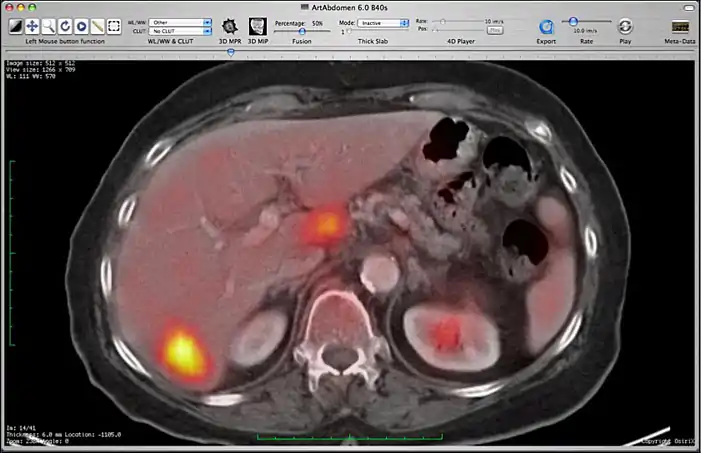

Image fusion between a CT and PET series.

You can control the fusion intensity with the “Fusion Percentage” slider from the toolbar. Note that if you close one of the two series, the fusion will be stopped. If you make a modification on the first series (CLUT, zoom, rotation, ...), these modifications will be applied to the second one.

Image fusion is also available for 2D and 3D reconstructions implying that you can use image fusion along with MPR, Volume rendering, etc...